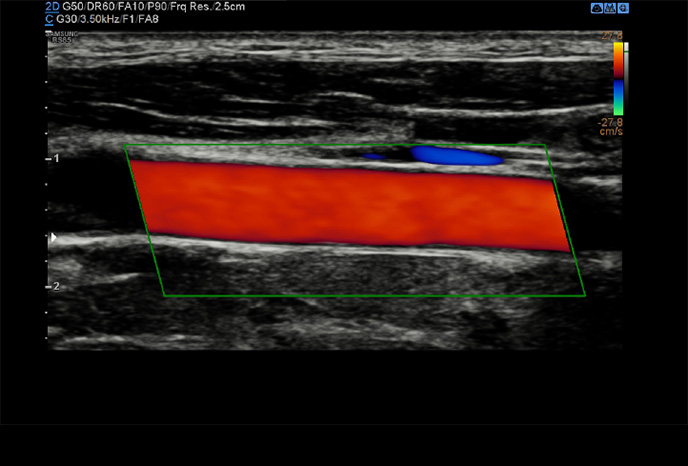

Arterial Analysis™

Arterial Analysis ™ detekuje funkční změny cév a poskytuje naměřené hodnoty, jako je tuhost, tloušťka intima-média a rychlost pulzní vlny karotidy. Protože funkční změny nastávají před morfologickými změnami, podporuje tato technologie včasné odhalení kardiovaskulárních onemocnění.

AutoIMT+

AutoIMT + je screeningový nástroj pro analýzu potenciálního rizika kardiovaskulárních onemocnění u pacientů. Umožňuje snadné měření tloušťky intima-media přední i zadní stěny karotidy jedním kliknutím.